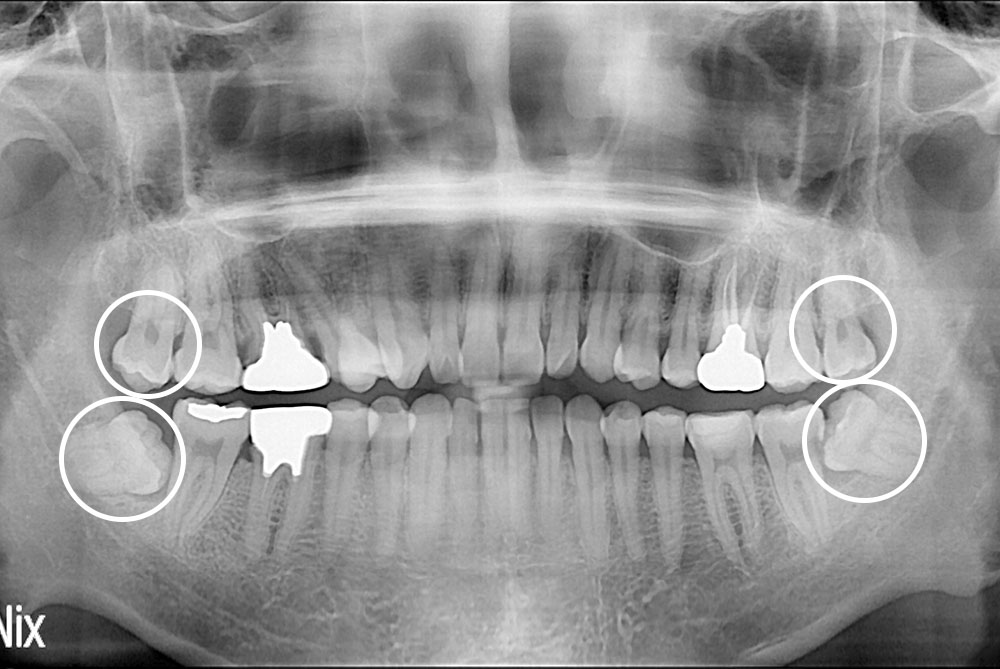

[사랑니] 매복 사랑니 발치

PX20230228_161958_5373_52137218.jpg

치료후 : 2023-02-28

세종치과는 구강악안면외과학 박사이신 원장님이 발치하는 치과입니다.